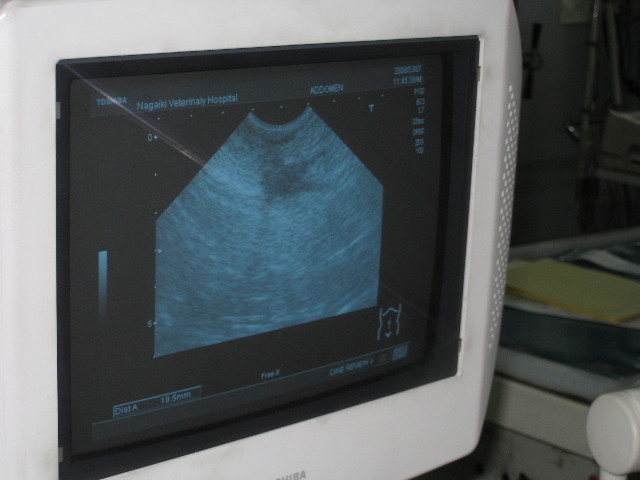

エコーも撮った。

●上部に黒っぽく写っているのが膿。(上がおへそ側)

●脾臓に腫瘍ではないが2〜2.5cmくらいの“かすかな腫れ”のようなものが見つかった。

こちらは一時的なものと思われるので経過観察。

●腎臓に異常なし。

●膀胱炎はない。